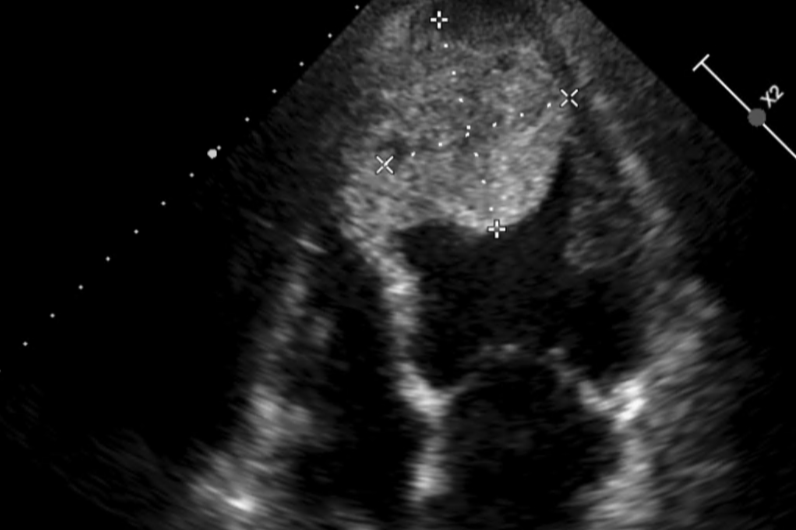

超音波檢查發現心臟有五公分大的血栓。